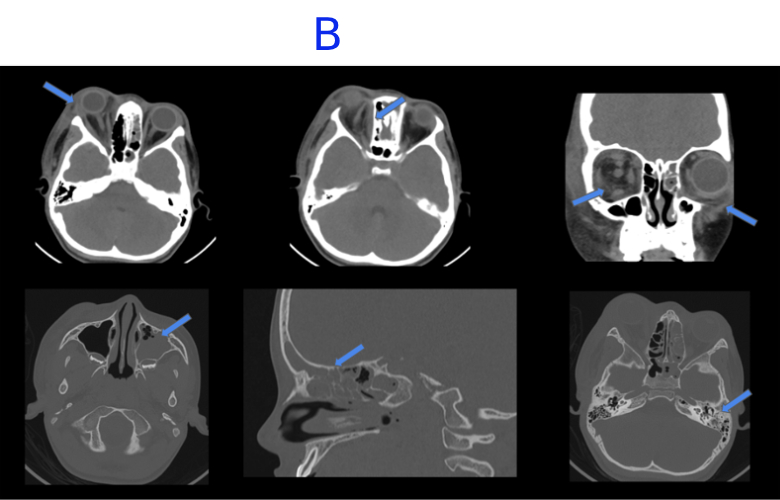

B. FINDINGS – CT PNS WITHOUT IV CONTRAST - DAY 2

B. Mild interval increase in hypodense collection along medial wall of right orbit. There is interval appearance of edema and fat stranding in periorbital soft tissue and preseptal space in the left orbit. Near complete mucosal opacification with bubbly secretions of left maxillary, ethmoid, frontal and sphenoid sinus with bubbly secretions. Mild mucosal thickening in the right ethmoid and sphenoid sinus.Opacification in left middle ear cavity and left mastoid air cells.